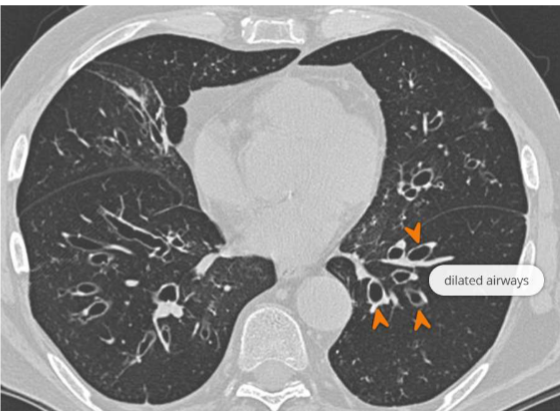

High Resolution CT – gold standard → Signet ring sign: bronchus > accompanying pulmonary artery